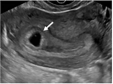

2.输卵管间质部异位妊娠:输卵管间质部异位妊娠较罕见,指受精卵着床于输卵管间质部(嵌入子宫肌壁内的输卵管近端部分)(图4)。超声诊断要点包括:(1)子宫与妊娠囊间滑动征阴性;(2)三维冠状切面重建图像显示子宫肌层部分包绕妊娠囊(妊娠囊周边子宫肌层组织呈“爪形征”),或子宫内膜与妊娠囊间可见薄层肌层组织;(3)间质线征仅偶见(图5),但该征象诊断输卵管间质部异位妊娠特异度较高。应避免使用‘宫角妊娠’或‘宫角异位妊娠’。

图5 间质线征超声图像。图为33岁孕妇(孕6周0天)经阴道超声横切面灰阶图像,显示右侧输卵管间质部异位妊娠(实线箭头)。除输卵管间质部异位妊娠特征性超声表现外,另可见一纤细高回声线(虚线箭头)连接子宫内膜与异位妊娠囊,为“间质线征”(图5译自参考文献[1])